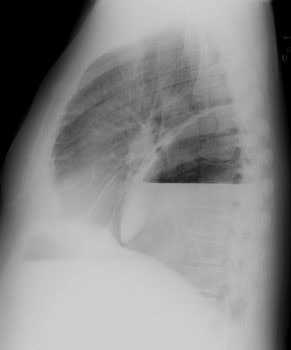

CXR: On CXR the abnormality can be localized to the pleural space because of its lenticular shape (forms obtuse angles with the chest wall, while a lung abscess is usually round with acute angles). An air-fluid level associated with an empyema is usually longer on the lateral film [7].| Empyema:

The CXR demonstrates a large, lenticular shaped air-fluid

level in the

right pleural space |